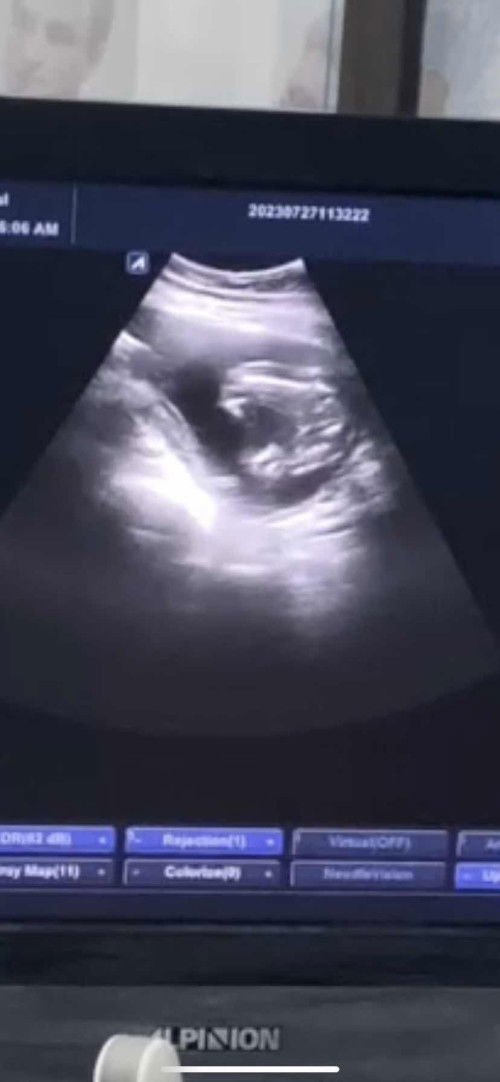

28 วีค น้ำหนักขึ้นเท่าไรกันบ้างคะแม่ๆ

บ้านนี้ 28 วีค ขึ้นมาแล้ว 8 โล กังวลว่าจะมากเกินไป เพราะก่อนท้องแม่หนัก 63 แล้วค่ะ ตอนนี้ 71 แล้ว 😂 #ท้องแรกคะ อยากปรึกษาแม่ๆ กินยังไงให้ลงลูกบ้างคะ ไม่อยากให้ค้างที่แม่เยอะเลยค่ะ กลัวลดไม่ลง #ขอคำแนะนำหน่อยค่ะ